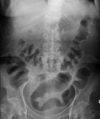

Large bowel obstruction